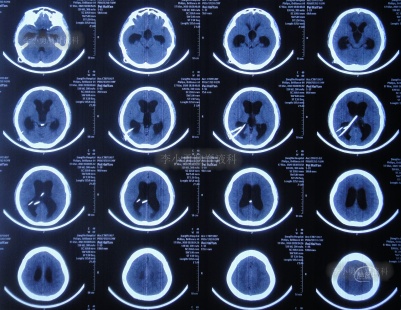

图-18:2020年4月19日

图-19:2020年4月19日头颅CT

入院治疗11天即2020年4月22日, 查头颅CT示脑室缩小,出血消失(图-20),头晕呕吐消失。

图-20:2020年4月22日头颅CT

入院治疗18天即2020年4月29日,进行了脑室腹壁外引流术,头颅CT示脑室缩小,脑室内仅有1根管(图-21)。

图-21:2020年4月29日头颅CT